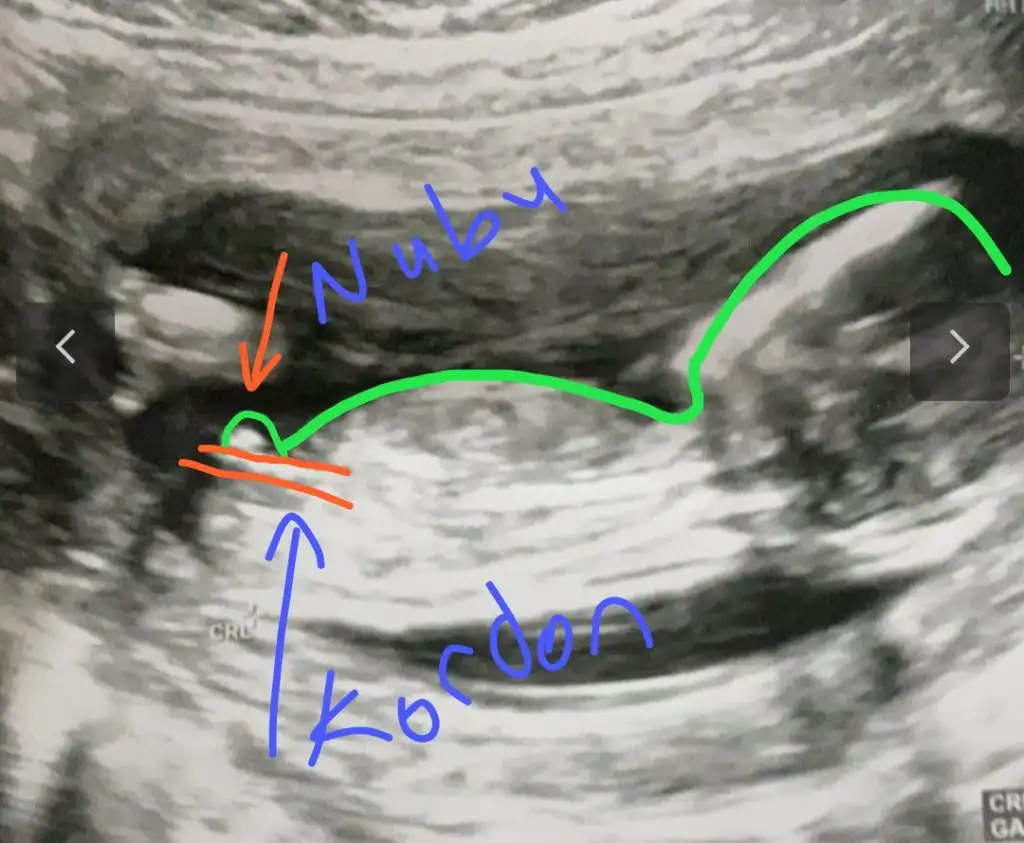

dr soylemeden siz gorun genital nub teorisi ( bebegin cinsiyeti)

Merhaba tekrar yükledimm ama bakabilir misiniz :)